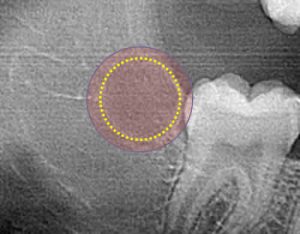

An over-ablated tooth bud will result in tooth agenesis, but increases the risk of adverse long-term side effects such as damage to the adjacent tooth or nerve damage

Zero3 technology controls the 20-40 second ablation process to gently warm the targeted tooth bud tissue (circled) from the center outwards to clinically induce prescribed molar agenesis while not significantly effecting adjacent tissues.